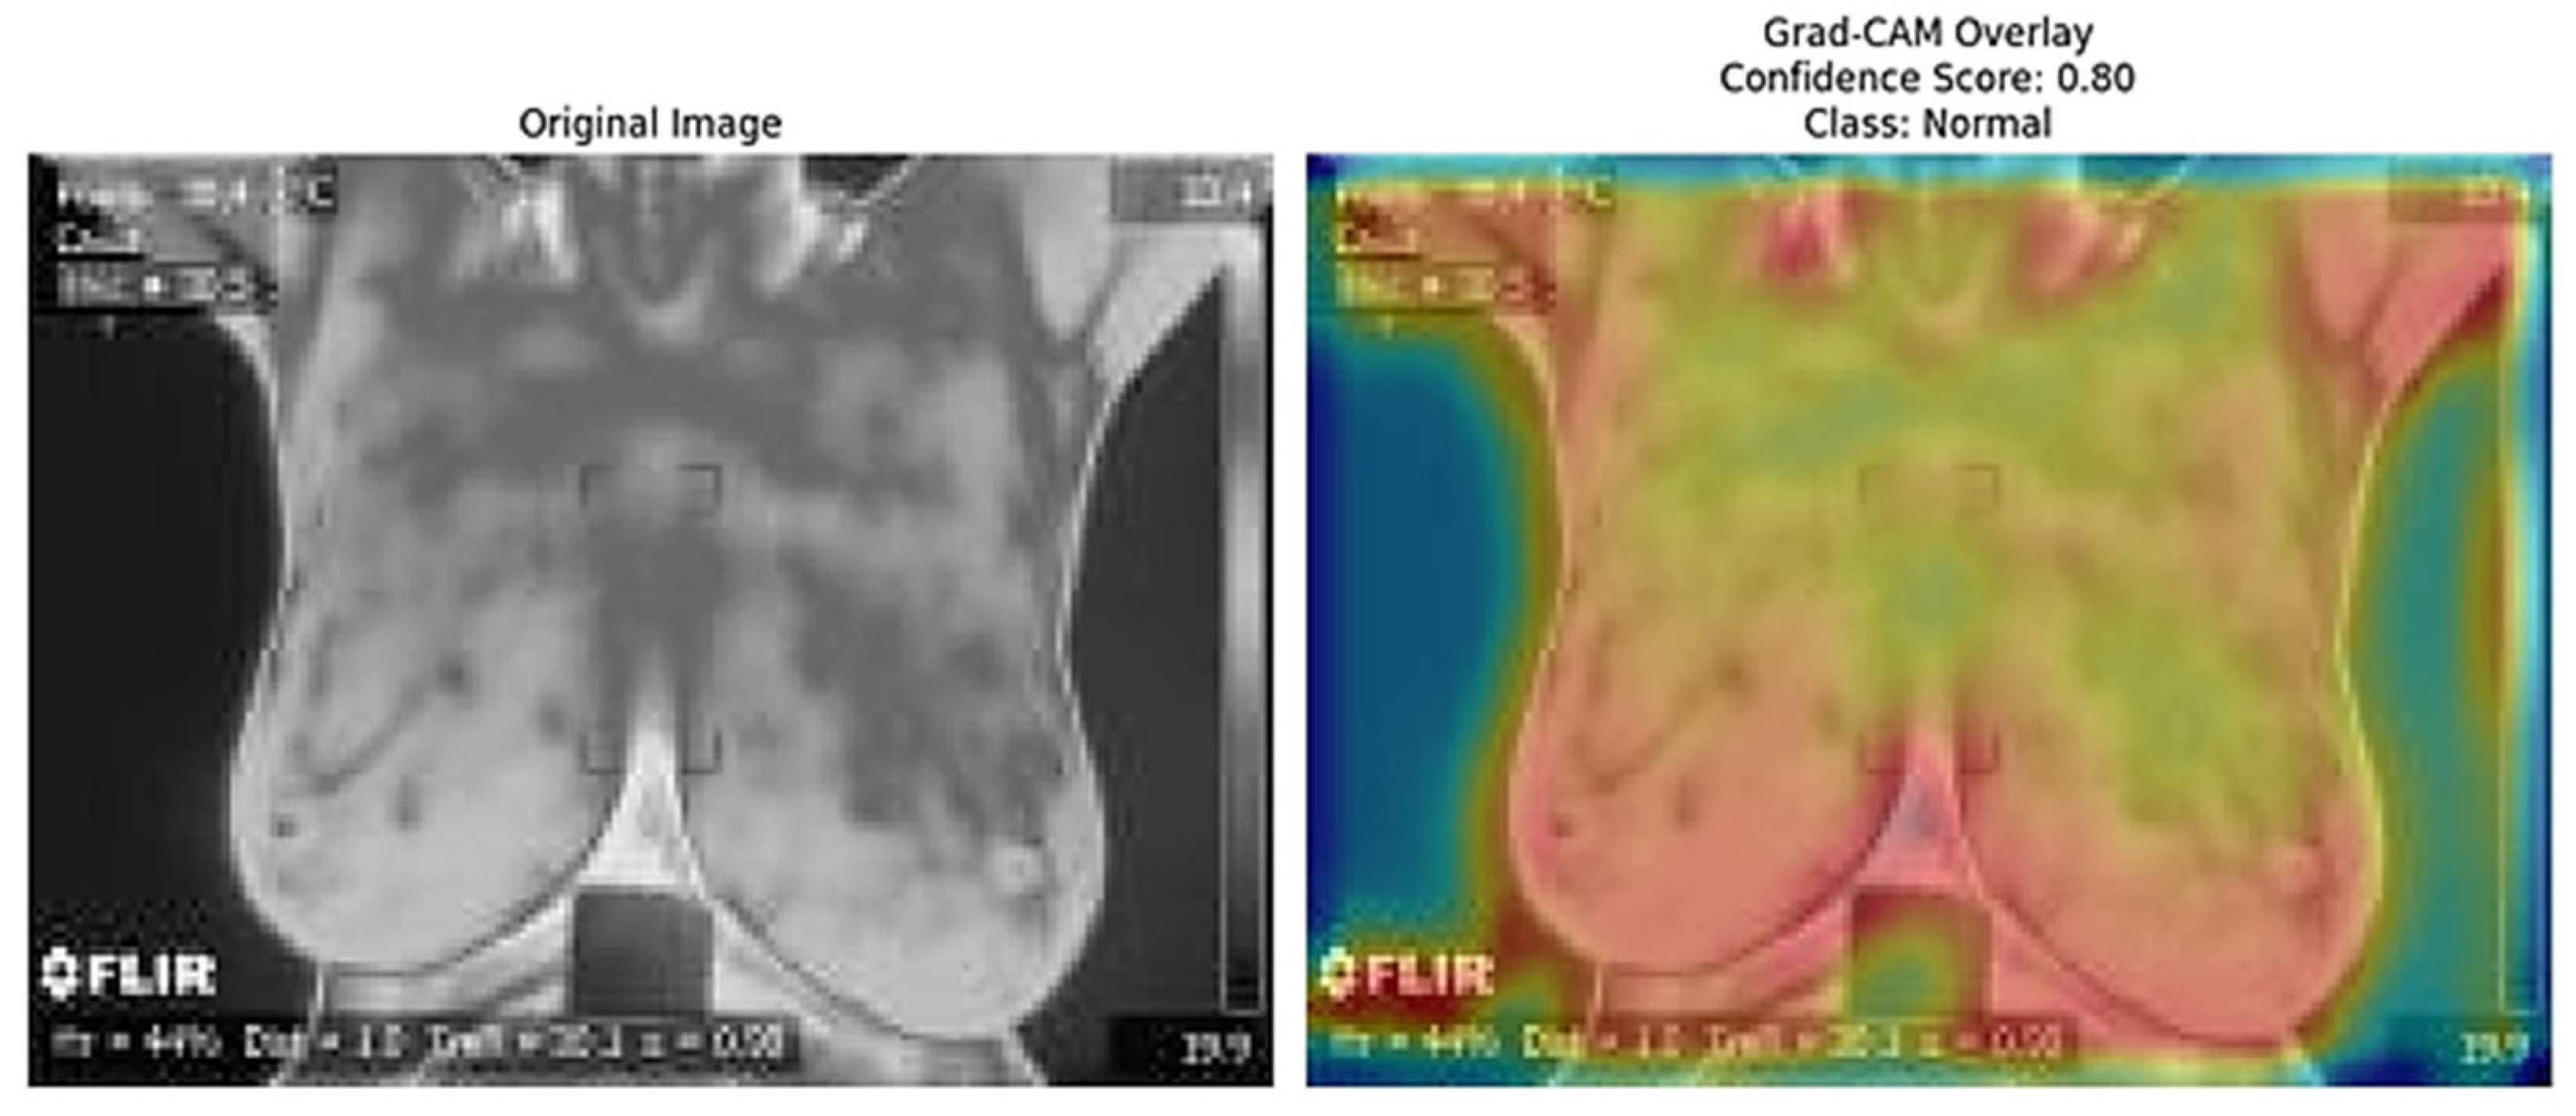

The Grad-CAM [41] overlays provide an essential layer of explainability to the ResNet152 + SVM model by highlighting regions of interest (ROI) that significantly influence the model’s predictions. These heatmaps, specific to each predicted class (e.g., normal, sick, malignant, benign), offer class-specific activation maps, shedding light on how the model differentiates among categories. By incorporating confidence scores (e.g., 0.80, 0.85) alongside these visualizations, clinicians can better understand and trust the model’s decision-making process. This approach directly addresses the “black-box” nature of deep learning models by visually explaining their predictions. Moreover, Grad-CAM overlays emphasize biologically relevant regions, such as abnormal heat patterns [56], as depicted in Figure 15, Figure 16, Figure 17, Figure 18 and Figure 19, enhancing the model’s interpretability and robustness in feature extraction. These insights validate the model’s focus areas against clinical knowledge and bridge the gap between AI-driven predictions and practical clinical applications, paving the way for greater trust and usability in real-world diagnostic settings.

Figure 15.

Grad-CAM Overlay for Normal Class (the original thermal image (left) alongside the Grad-CAM overlay (right) highlights the regions contributing to the model’s prediction of the “Normal” class with a confidence score of 0.80).